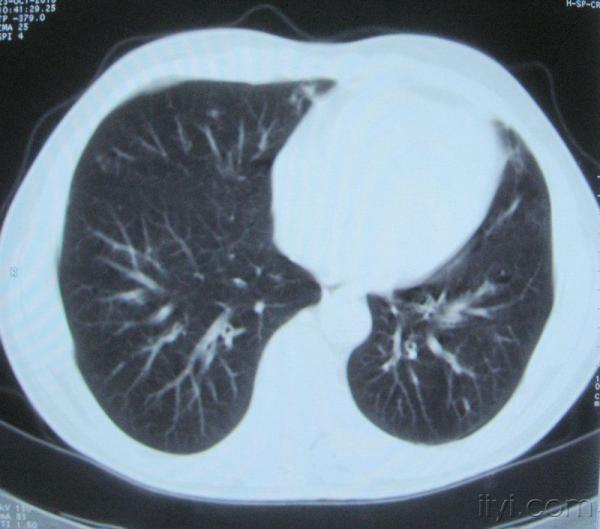

男。60岁,胸片示支气管炎治疗后复查CT。

你指那个肯定是淋巴结,中央系坏死,这很常见,特别在双侧腹股沟会经常看到。这个双侧腋窝及纵隔见多发小淋巴结征。

根据位置考虑应该是淋巴结,密度不均,是因为肿大的淋巴结中心液化坏死